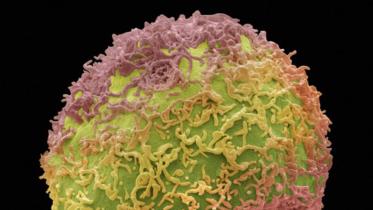

Fungus used in traditional medicine can fight cancer: Chinese researchers

Chinese scientists have found evidence that a fungus used in traditional Chinese medicine widely sought by the public for its healing powers, also carries anti-cancer benefits.